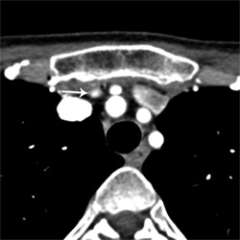

Figure 1a. Parathyroid 4D-CT showing a parathyroid adenoma in an abnormal position within the carotid sheath, missed during a prior surgery. CA= Carotid artery.

Figure 1b. Parathyroid 4D-CT showing a parathyroid adenoma in an abnormal position within the carotid sheath, missed during a prior surgery. CA= Carotid artery.